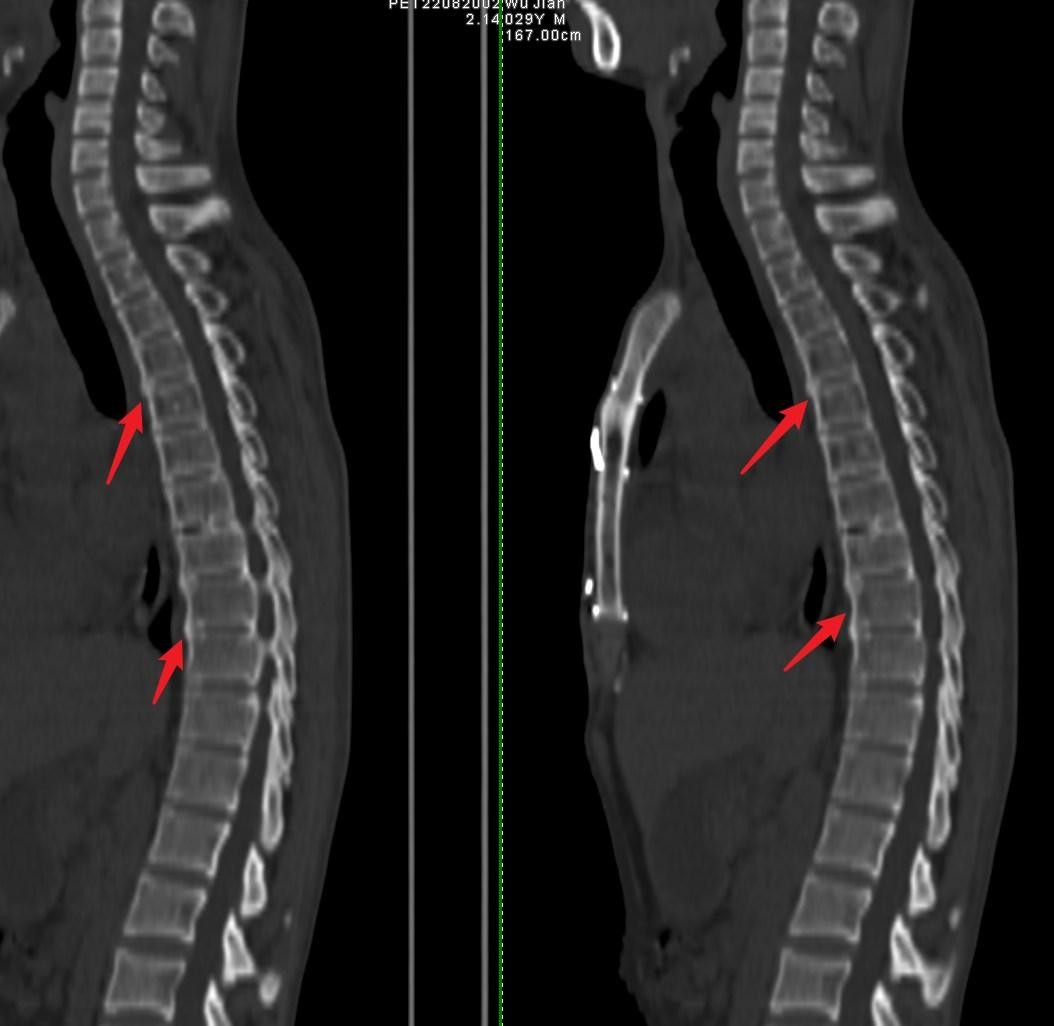

图2:早期表现:29岁男性↓

部分椎体边缘骨质增生、椎间隙狭窄,脊柱轻度后凸,双侧骶髂关节间隙变窄,关节面不光整并可见骨质增生、硬化。↓